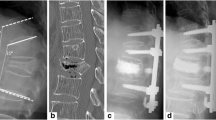

Both spinous processes were prepared for allograft passage by predrilling a 3.2-mm hole from one side to the other through the middle of the spinous process. The holes were overdrilled using a 5-mm drill bit, taking care not to create an iatrogenic fracture (Fig. 1). A gracilis or semitendinosus tendon allograft (AlloSource, Centennial, Colorado) was prepared, thinning the allograft to a maximum diameter of 4 mm and reinforcing one end of the tendon with a Fiberwire No. 2 (Arthrex, Naples, Florida) using a 2-cm-long Krackow suture [14] (Fig. 1). For vertebropexy, the tendon graft was looped twice. The other end of the tendon was similarly reinforced with a Fiberwire No. 2, creating a loop in addition to the Krackow suture (Fig. 1). Thereafter, the allograft was pulled through the previously drilled holes in a double loop technique (Fig. 2a–c). An extension load of 5Nm was applied via the static testing machine to simulate a prone position with physiological extension of the lumbar spine. The Fiberwire was knotted using the cow hitch technique (Fig. 2d): a double-stranded knot configuration with a loop on one side, secured by four half hitches. This technique is biomechanically stronger and stiffer compared to several other conventional knots [15]. The knot was tightened with a force of 70N using a needle holder (Fig. 2e). The applied force was objectified with a force gauge. Finally, the second end of the tendon was sutured to the loop (Figs. 2f, and 4b).

Midline decompression and interlaminar vertebropexy

The supraspinous and interspinous ligaments were sharply removed with a Leksell rongeur, and the two spinous processes were partially removed. Midline decompression was performed with the osteotome, taking care not to harm the facet joints. The remaining ligamentum flavum was exposed and removed from cranial to caudal.

Two tendon allografts were reinforced in the same manner as described above (Fig. 1). Then the reinforced ends of the tendons were carefully passed under the laminae on both sides from cranial to caudal (Fig. 3a). A rongeur was used to pull the tips of both tendons up through the distal interlaminar window or above the inferior lamina (Fig. 3b). The segment was reloaded with 5Nm extension and the Fiberwire was knotted bilaterally using a cow hitch and tightened with a force of 70N (Fig. 3c). The remaining part of the tendon was sutured to the loop (Fig. 3D, Fig. 4c).

Depending on the integrity of the dorsal structures after decompression two surgical techniques were developed: (1) interspinous vertebropexy following posterior microsurgical decompression with preservation of midline structures and (2) interlaminar vertebropexy following posterior decompression without preservation of midline structures. These structures mostly provide passive stability in flexion [16]. With both vertebropexy techniques segmental stability could be increased for all directions of movement compared to prior decompression. Considering flexion–extension, vertebropexy reduced the ROM by more than 50% compared to the native segment.

When comparing the two vertebropexy techniques, the stabilizing effect of the interspinous technique was more pronounced. This can be explained by the smaller lever arm of the interlaminar technique compared to the interspinous technique, as the distance to the center of rotation, i.e., to the center of the disc, is smaller. A force of 70N for tightening the knot was arbitrarily chosen to not exceed the load to failure [18], to minimize the risk of iatrogenic fracture, and to use a force that could be easily achieved in the operating room.